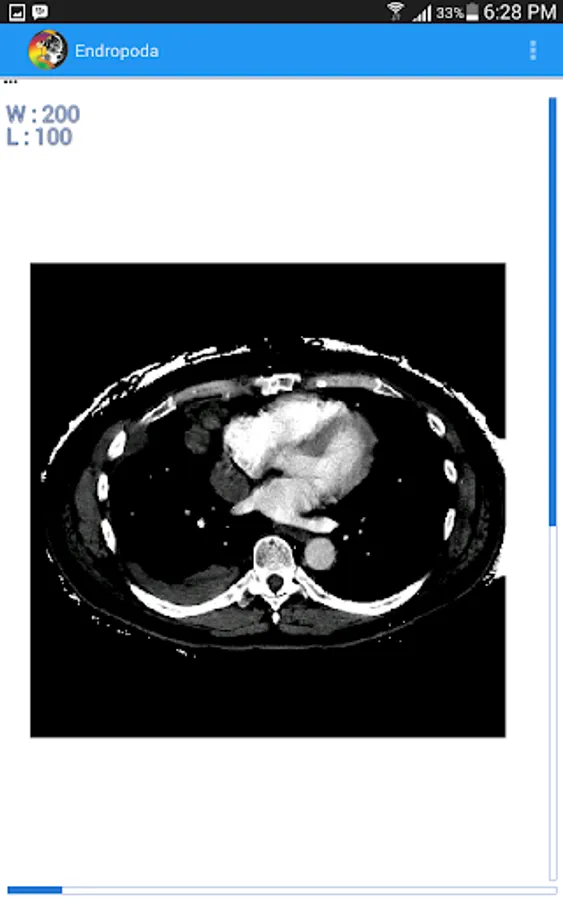

- HU mode : In this mode we can set the window width and window level of CT-Scan image to produce higher contrast higher contrast for certain organ, so it will be displayed better than another organ its surrounding. The basic principal of window technique is based on CT number. Where is CT number is a value related to attenuation coefficient of certain organ that can be used to distinguish an organ from another based on their attenuation coefficient.